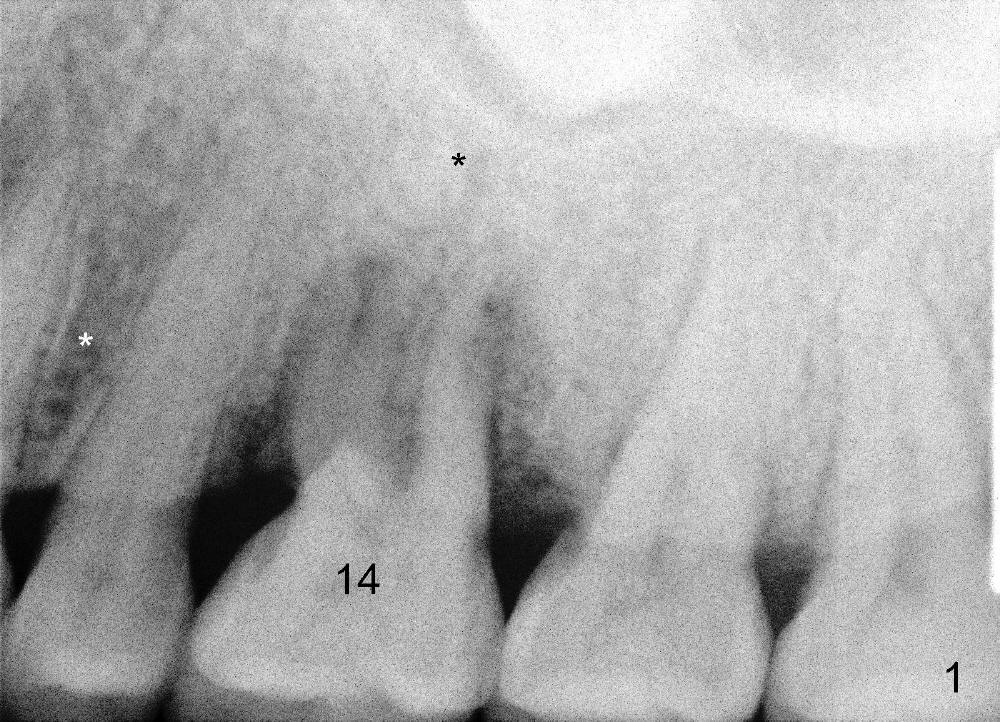

Bone density around the molars (including apical to #14) (Fig.1 black *) is higher than that around the premolar (white *). In fact the tooth has horizontal root fracture (Fig.2: <: CEJ), consistent with high bone density (strong mastication). An immediate implant is planned (Fig.3). After extraction, osteotomy starts at the buccal slope of the palatal (Fig.4 P) socket. Because of high bone density apical to the sockets, drills are required for osteotomy in the septum (type II bone) instead of osteotomes and primary stability is easily achievable (>60 Ncm). When a 7 mm implant (Fig.6 I)) is placed, the peri-implant gaps are much smaller (*) than that with a 4.5 mm tap (Fig.5 T). This helps bone grow faster toward implant. A long implant (17 mm) is necessary for this case to obtain primary stability in the apical one (double arrows in Fig.6). With reamers, a fair amount of autogenous bone is harvested during drilling, mixed with allograft and synthetic bone and placed in the remaining buccal (Fig.7) and palatal (Fig.8) sockets. The openings of the buccal and palatal sockets are covered with collagen dressing (C) and perio dressing. The latter is kept in place by a short abutment (Fig.6-8 A).